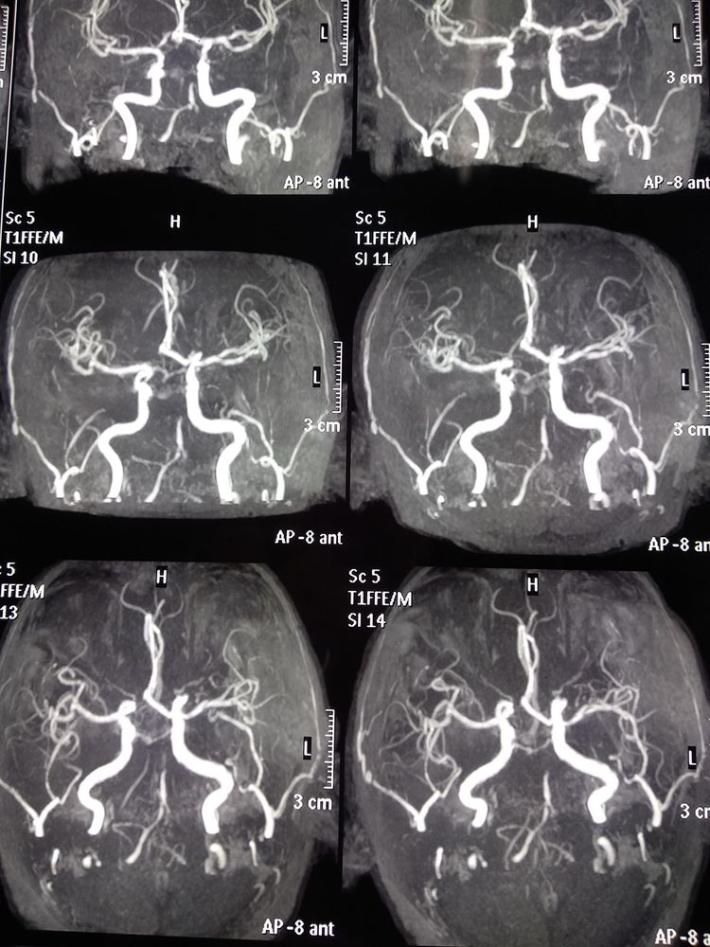

双侧颈内动脉

双侧椎动脉

左侧椎动脉

分析该患者:目前神志清楚,双侧肌力4级,基底动脉前向血流3级,且患者取栓术后可能需要支架植入术,术后需要常规双重抗血小板聚集治疗,与患者丘脑出血治疗相矛盾,拟病情平稳后择期支架植入术,综合考虑后,结束造影,中性治疗。